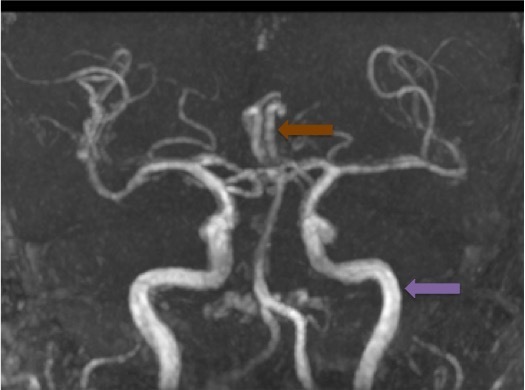

Voici l’angiographie par résonance magnétique (ARM) du polygone de Willis réalisée chez ce patient.

Question 4 : Concernant les structures légendées, quelles sont la/les proposition(s) exacte(s) ?

Artère cérébrale moyenne également appelée artère sylvienne.

Artère cérébrale antérieure gauche, naissant (hors variante anatomique) de la terminaison de la carotide interne homolatérale. Les deux artères cérébrales antérieures communiquent par une artère communicante antérieure dont la naissance est située à l’union de leurs deux premiers segments.

Artère cérébrale postérieure droite. Celles naissent du tronc basilaire communiquent avec le système carotidien via les artères communicantes postérieures (une de chaque côté).

Tronc basilaire, formé par l’union des deux artères vertébrales en intracrânien

Artère carotide interne gauche. La division de l’artère carotide commune en artère carotide interne et externe est située en extracrânien à hauteur de C4.

À noter que le polygone de Willis peut présenter de nombreuses variantes anatomiques qui peuvent avoir une répercussion en cas de pathologie artérielle (présence ou absence de suppléance via les anastomoses entre les systèmes carotidiens d’une part, carotidien et vertébro-basilaire d’autre part).